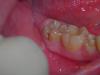

Доктор Саша Опубликовано 21 января, 2009 Поделиться Опубликовано 21 января, 2009 Как будем изолировать от десневой жидкости?(кроме лечения планируется герметизация фиссур) Ссылка на комментарий

Zlata-doctor Опубликовано 27 января, 2009 Поделиться Опубликовано 27 января, 2009 И еще... сюда как раз хорошо подойдет оптидам на пластмассовых клампах (Керр). Этот зуб очень проблемный, его легко можно запороть, я бы сделала рентген сначала. сколько лет ребенку? Ссылка на комментарий

Доктор Саша Опубликовано 29 января, 2009 Поделиться Опубликовано 29 января, 2009 сюда как раз хорошо подойдет оптидам на пластмассовых клампах (Керр). Этот зуб очень проблемный, его легко можно запороть, я бы сделала рентген сначала. сколько лет ребенку?8 Ссылка на комментарий